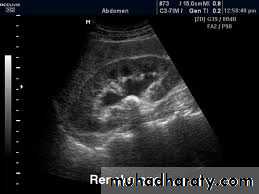

Ultrasound findings

1-Dilatation of the P.C.S. appears as multilocular fluid collection within central echo complex.-With more severe distention, dilated calyces appear as

Multiple cysts but communicating with each other unlike true cysts.

2-Stones larger than 5mm are easily seen on US but smaller ones may be missed.

-They produce intense echoes (hyperechoic) and cast acoustic shadows.